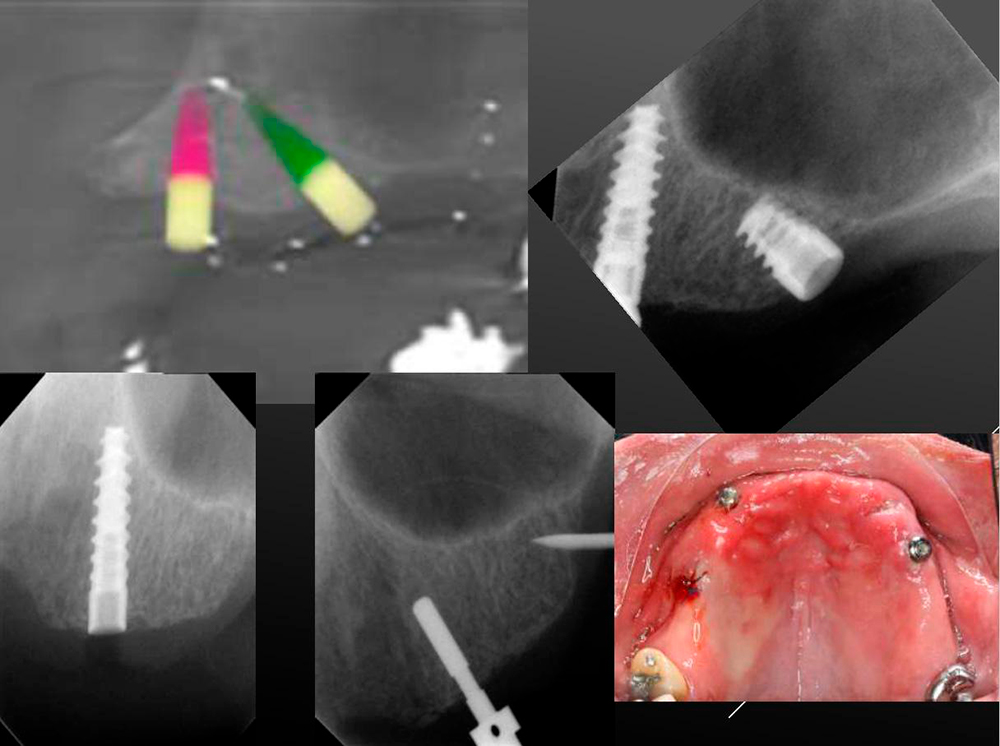

Implant zone 23 Bone available 7.8 x 13.2 Dsi Premium Green Line Implant 3.5x11.5

6.4 x 11.5 m, mm DSI Premium Green Line Implant 3.75 x 10. Density

HU 1332 bone type 1-2